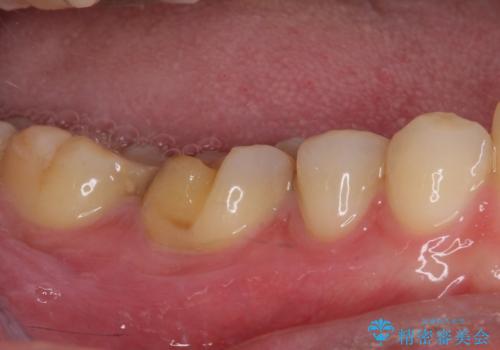

咬合力が強いため、強化セラミッククラウンでの補綴治療を行うこととしました。

強化セラミッククラウンは単一素材のため、非常に高強度でありますが色調は単調なものとなり、隣在歯と調和させることは困難です。